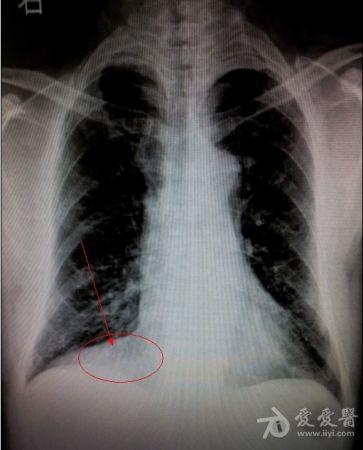

男,52岁,右心膈角是什么?

超越心包位置太多了,明显靠外了。肯定不是心包脂肪垫。如果的一个侧位就好了。提出一个可能“波浪膈”。欢迎质疑。

三角形的,结合透视看看,肺部张不能除外的。

同意楼上,心包脂肪垫。